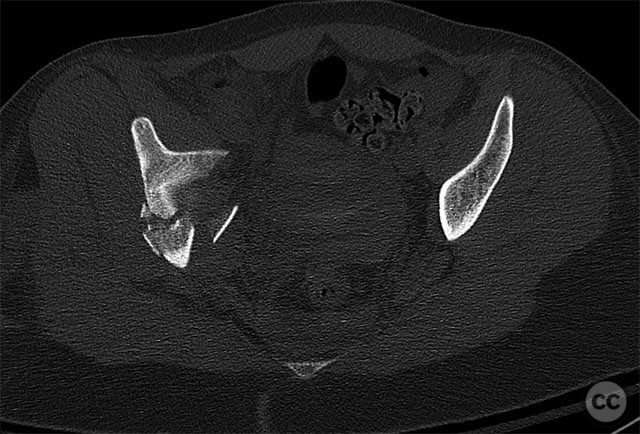

Clinical and radiological findings:  A 19-year-old female sustained a high-energy injury in a motor vehicle accident. Initial AP pelvic radiograph demonstrated a right-sided, displaced, comminuted associated both column acetabular fracture (AO/OTA 62C3), with a separate fracture fragment involving the greater sciatic notch (GSN). The right sacroiliac (SI) joint was incompletely disrupted. Surface rendered CT images confirmed the complex fracture morphology, including the separate GSN fragment and the SI-sacral injury, which rendered the typical posterior iliac fragment non-intact. Axial CT at the acetabular dome level revealed multiple displaced fragments and provided further detail regarding soft tissue involvement.